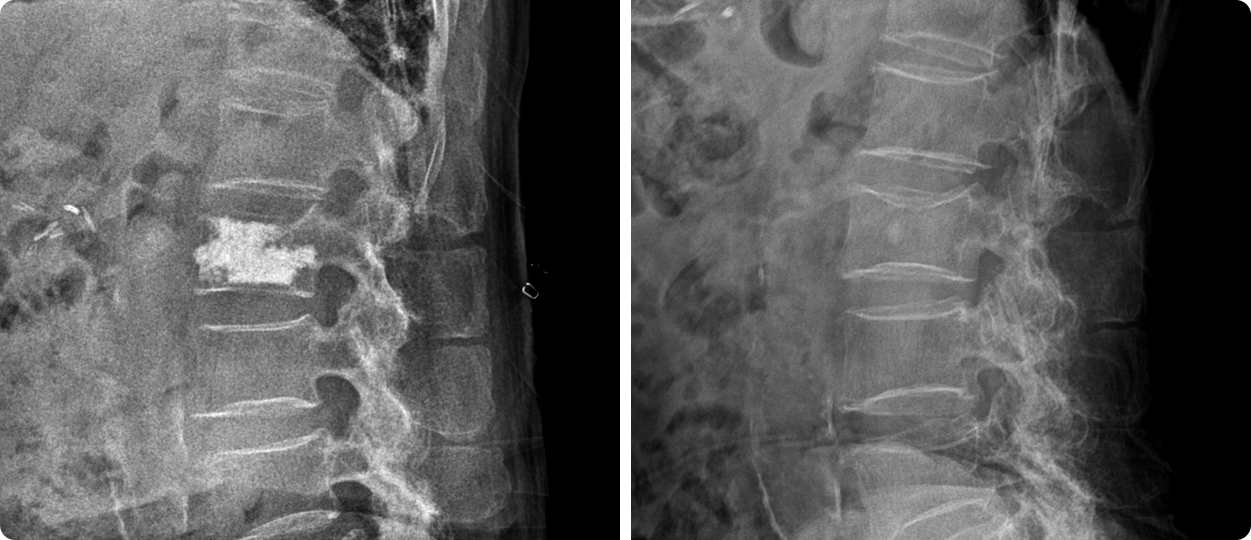

척추체 성형술은 척추 손상부위에 뼈 시멘트를 주입해 통증을 감소시키며 척추의 불안정성을 제거해주고

골절이 진행되어 척추체 높이가 가라앉는 것을 막고 척추 안정화를 통해 통증을 감소시키는 시술입니다.

골다공증이나 척추 종양 등으로 허리뼈가 약해져 주저앉았을 때 특수 바늘을 이용하여

척추뼈에 척추 뼈 강화제(골시멘트)를 넣어주는 시술로, 척추뼈가 더 이상 주저앉는 것을 최대한 막고 초기단계에서도

복원 불가능하거나 extension(확대) 시 척추체 높이가 증가하는 환자에게서는 일부 높이 복원이 가능합니다.

전신마취가 아닌 부분 마취 후 간단한 수술방법으로 조기 보행이 가능하며, 심하게 무너진 척추골의 높이가

가라앉는 것을 막고 척추 안정화를 통해 통증을 감소시킬 수 있습니다. 회복기간도 짧아 많이 적용되는 치료 방법입니다.